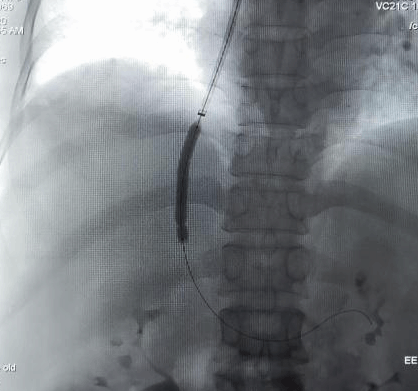

TIPS技术: